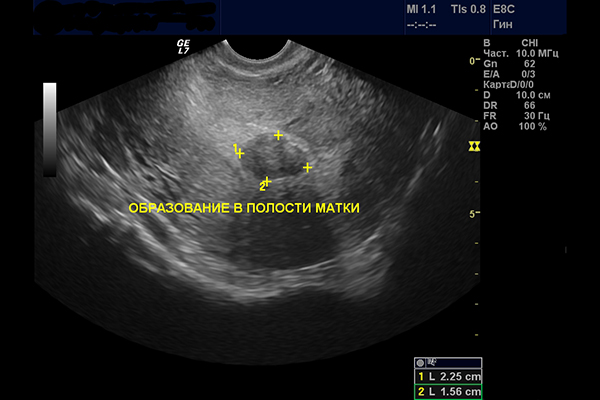

К заключению исследования УЗИ практически всегда прилагается снимок. Так как же выглядит миома матки на УЗИ?

На фото четко видно данные опухоли в детородном органе. Узловые новообразования миоматозного характера на снимке УЗИ выглядят, как выпуклости округлой формы в полости или слизистой матки.

При исследовании можно определить их размер, однако это становится возможным не во всех случаях и часто зависит от расположения новообразования.

На фото ниже показано УЗИ субмукозной миомы.